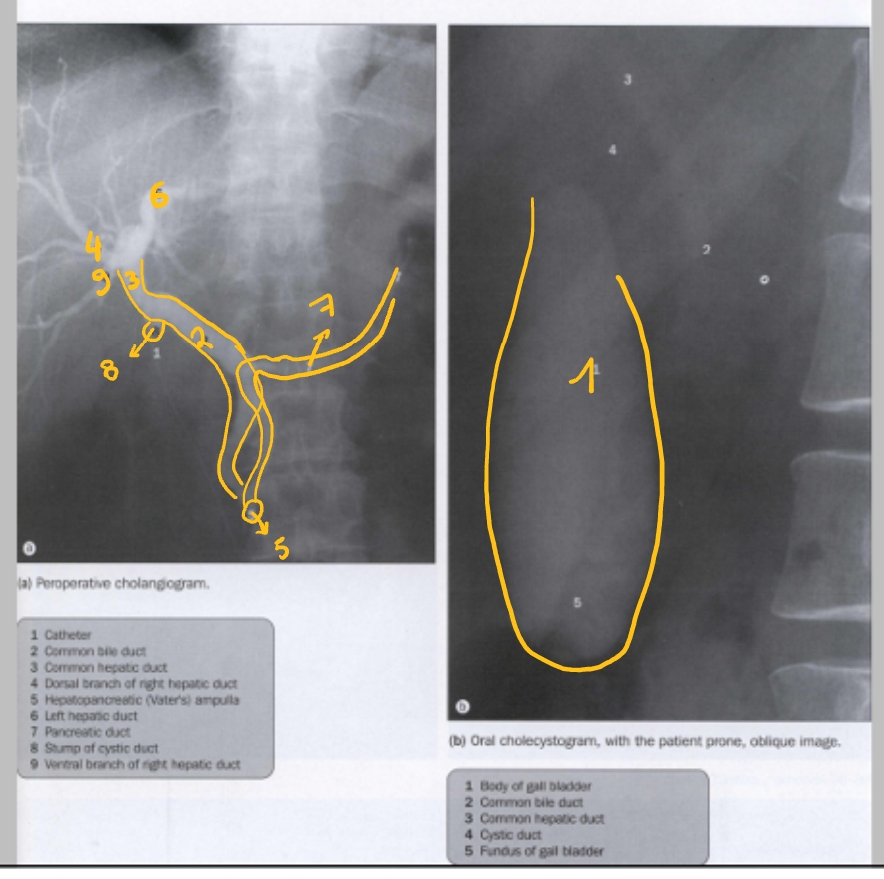

galblaas

ductus choledochus

ductus hepaticus communis

ductus hepaticus dexter, ramus dorsalis

papil van Vater (met ampulla)

ducuts hepaticus sinister

ductus pancreaticus major (van Whirsung)

ductus cysticus

ductus hepaticus dexter, ramus ventralis